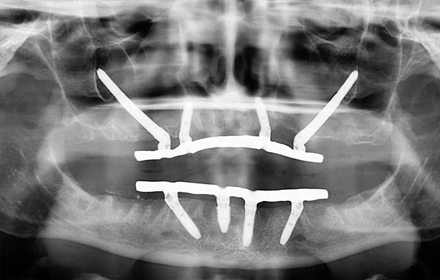

Имплантация all-on-6 V-II-V с установкой имплантов транссинусально для верхней челюсти

Хирург-имплантолог, пародонтолог, ортопед Жиленко Евгений

Россия, Москва